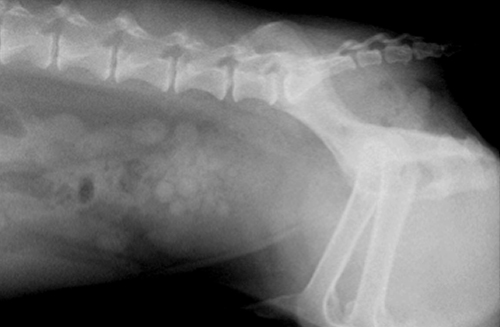

犬 膀胱結石・尿道結石 チワワ 10歳11ヶ月齢 去勢オス 71kg 頻尿と血尿、排尿障害を主訴に来院 腹部と陰茎の触診検査にて結石症が疑われたため、 レントゲン検査を行い、膀胱結石および尿道結石、腎臓結石と診断した 尿道内にぎっしりとつまった結石は、カテーテルにて膀胱内に押し戻し、膀胱切開にて膀胱結石を摘出した 腎臓結石はに対する外科処置は、腎臓. 犬の膀胱結石 更新日時: ミニチュアダックスフンド、オス (去勢)、11歳 《主訴》血尿、排尿しづらい (少量ずつしか出ない) 《検査》①腹部レントゲン検査 膀胱に結石と思われる不透過性陰影を多数確認 ②腹部超音波検査 膀胱内に結石と思われるシャドーを引く高エコー物を多数確認 ③尿.

犬 膀胱結石 尿道結石 川崎区の動物病院 たかはし犬猫病院

犬の尿道および膀胱結石 彩りブログ

犬の尿道 膀胱結石 メルどうぶつ病院 栃木県小山市の動物病院 犬猫 うさぎ

犬の尿石症 膀胱結石 尿道結石 きむら動物診療室の診療記録と医療情報